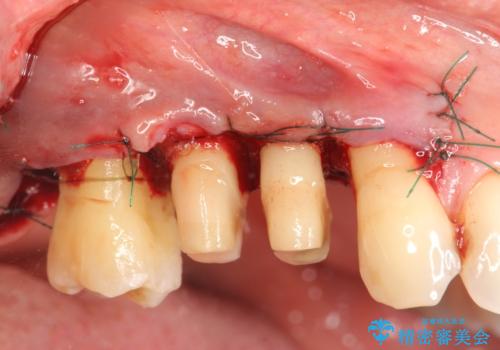

今回連結補綴を行うにあたり、歯周病の問題を解決するために再生療法・歯周ポケット除去手術を、またより歯の神経を保存し力に対抗できる環境を整えるために小矯正を行い精度の高いメタルボンドクラウンを製作することができました。

- 外科手術のため、術後に痛みや腫れ、違和感を伴います

- 歯周組織再生治療は患者様の状態によって術後の経過が異なります(見た目が改善しない場合もあります)